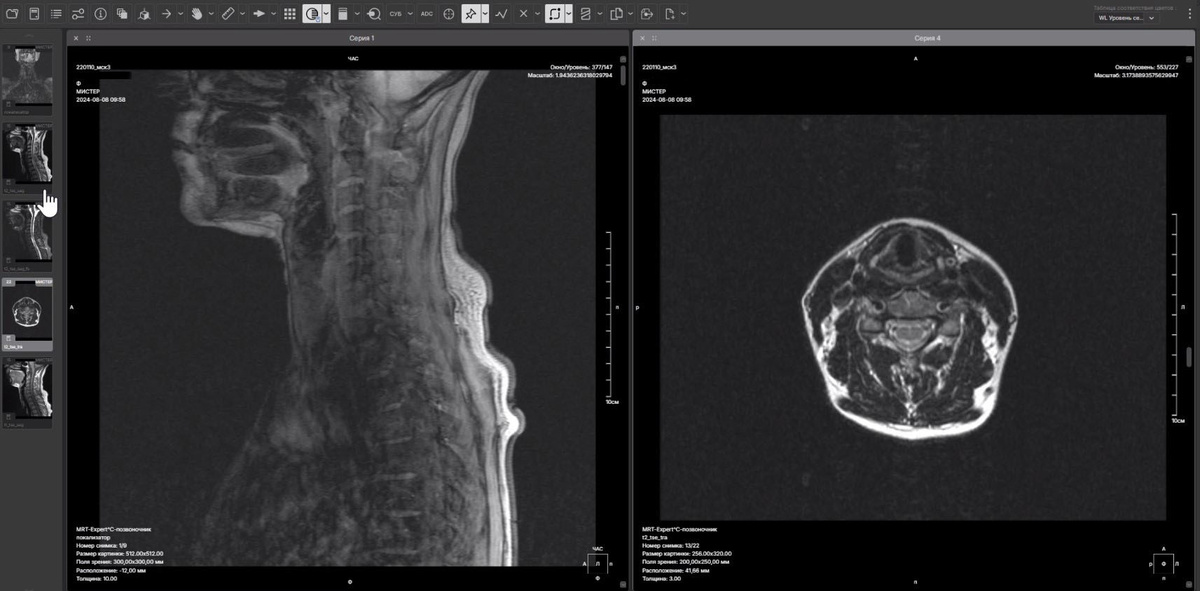

Разработка онлайн DICOM-просмотрщика: как мы создали мощный инструмент для медицинской визуализации

• Инструментарий врача-рентгенолога, позволяющий работать с изображением: увеличивать, вращать, переключать с 2D на 3D-реконструкцию, измерять, размечать, сравнивать и т.д.

2. Проектирование интерфейса

Мы сосредоточили усилия на создании интуитивно понятного и удобного интерфейса, который одновременно оставался бы привычным и основывался на традиционных программных решениях. Это позволяет пользователям легко загружать, просматривать и обрабатывать изображения. В интерфейс были включены функции масштабирования, поворота, аннотирования и измерения, а также возможность переключения между 2D и 3D режимами.

Возможность просмотра как 2D, так и 3D изображений, включая аксиальные, корональные и сагиттальные виды, облегчает интерпретацию и анализ данных. Это позволяет медицинским работникам более эффективно оценивать изменения в состоянии пациентов.